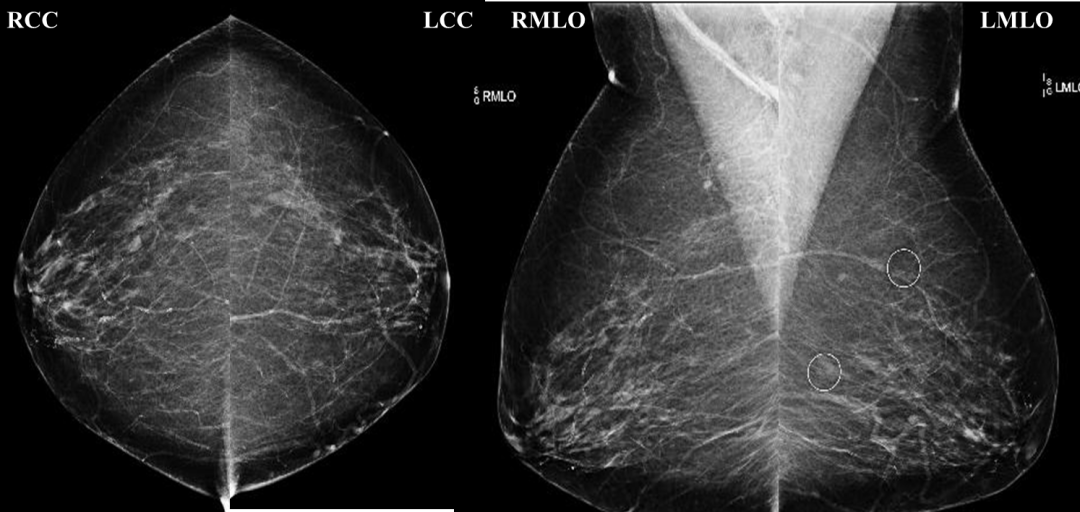

某女性患者,45岁,曾彩超检查诊断乳腺增生数年,医院引进钼靶设备后便立即进行了预约,通过钼靶检查,发现左乳腺结节,考虑 BI-RADS4c,后经过穿刺进一步明确,最终选择了手术治疗,病理诊断最后结果为浸润性乳腺癌,因发现及时、治疗得当,目前该患者已康复出院。

清晰显示乳腺组织结构

市人民医院放射科主任汪云介绍,目前用于诊断乳腺癌的方法很多,在众多非损伤的方法中,仍以钼靶X线乳腺摄影最为成熟,它能清晰显示乳腺各层组织,可以发现乳腺增生,各种良恶性肿廇以及乳腺组织结构紊乱,可观察到小于0.1毫米的微小钙化点及钙化簇,是早期发现、诊断乳腺癌的最有效和可靠的方式,尤其对于临床不可能及的,以微小钙化簇为唯一表现的早期乳腺癌具有特征性的诊断意义。对于40-70周岁的妇女,推荐每年1次乳腺钼靶X线检查。